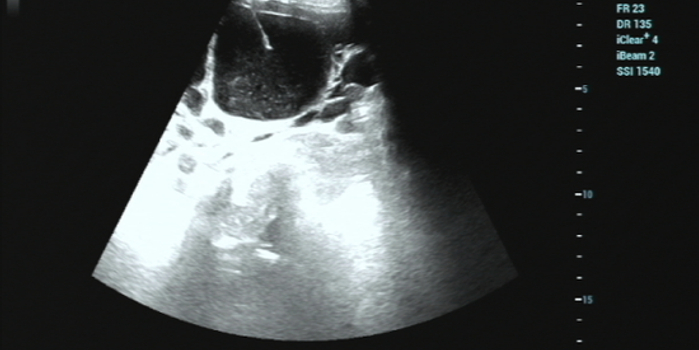

1. 精准定位: 超声就像医生的“透视眼”。在治疗前,超声仪器会清晰地显示囊肿的大小、位置,以及与周围大血管、脏器的关系,规划出最安全的进针路线。

2. 细针穿刺: 局部麻醉后,医生用一根很细的穿刺针(比平时打针的针头粗不了多少),在超声的实时监控下,精准地刺入囊肿中心。

3. 抽液硬化:先将囊内的液体抽干净,然后注入硬化剂(通常是无水酒精或聚桂醇)。这个硬化剂的作用是破坏分泌囊液的“囊壁细胞”,让它失去分泌功能,就像把水泡的内壁“烫”一下,让它粘合在一起。

4. 告别囊肿术后,囊肿会慢慢萎缩、被身体吸收,最后消失。